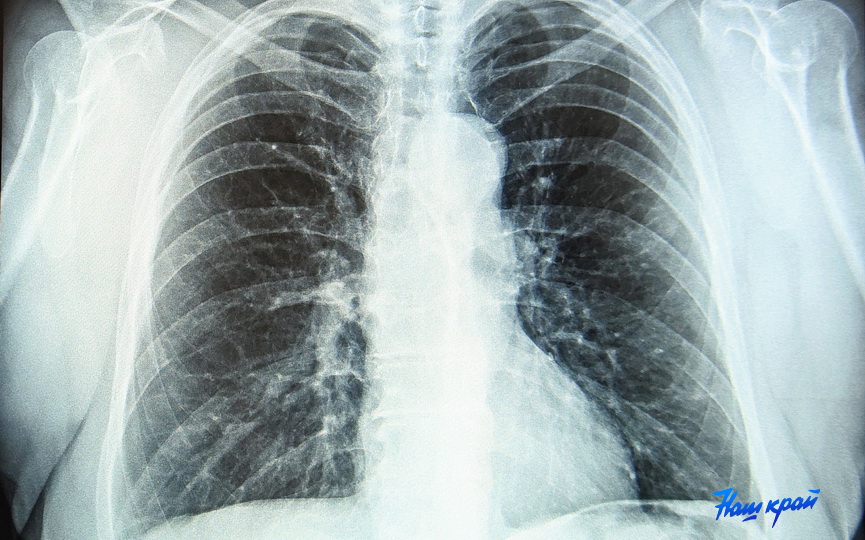

После пандемии ковида многие люди стали посещать пульмонологов - кто-то из-за проблем, а кто-то для профилактики. Оставляет ли ковид пожизненный отпечаток на легочной ткани, в проекте БЕЛТА "В теме. Здоровье" узнали у врача-пульмонолога Сергея Федорова.

- Если это была большая тяжелая пневмония, то чаще всего (по крайней мере, из тех пациентов, которых я видел за несколько лет) оставались какие-то изменения после перенесенного воспалительного процесса. Хотя не у всех.

- В зависимости от объема. Если их много - да, развивается дыхательная недостаточность, которая может проявляться при физической нагрузке. Наверное, можно отметить то, что как только ковид закончился, стало больше пациентов с бронхиальной астмой. Я не готов сказать, с чем это связано, но их стало больше. Возможно, произошли какие-то изменения у тех людей, которые переболели.